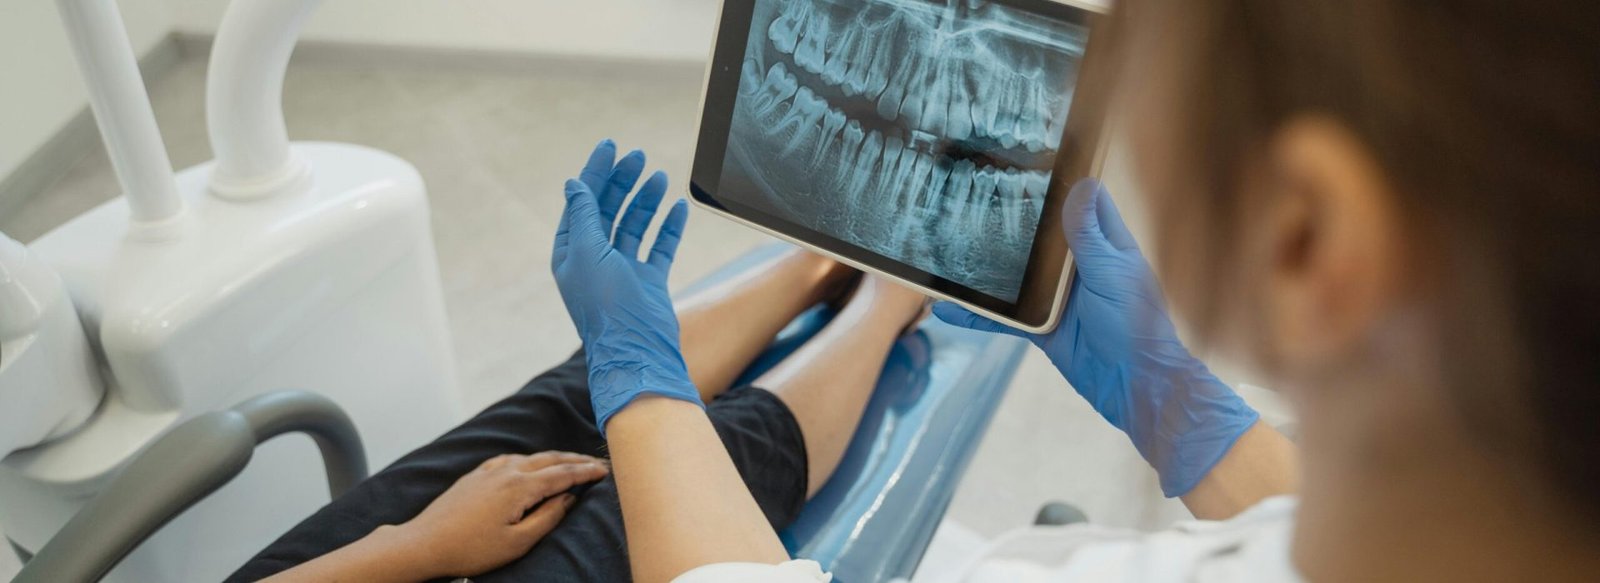

At Gelos Dentistry, we start with an in‑house 3D CBCT scan. This gives us a clear, three‑dimensional view of your jaws – bone height, width, density, nerve canals, sinus spaces – everything we need to see before touching the bone. On a computer, we then plan where each implant should go, at what angle, and to what depth.

If implants look like a good option, we move to a 3D CBCT scan. The scan is quick and painless; you simply stand still while the machine rotates around your head. Within minutes, we can see detailed cross‑sections of your jaws on the screen.

This step is done right at our dental clinic in Tricity, so there’s no waiting for reports to come from a different centre.